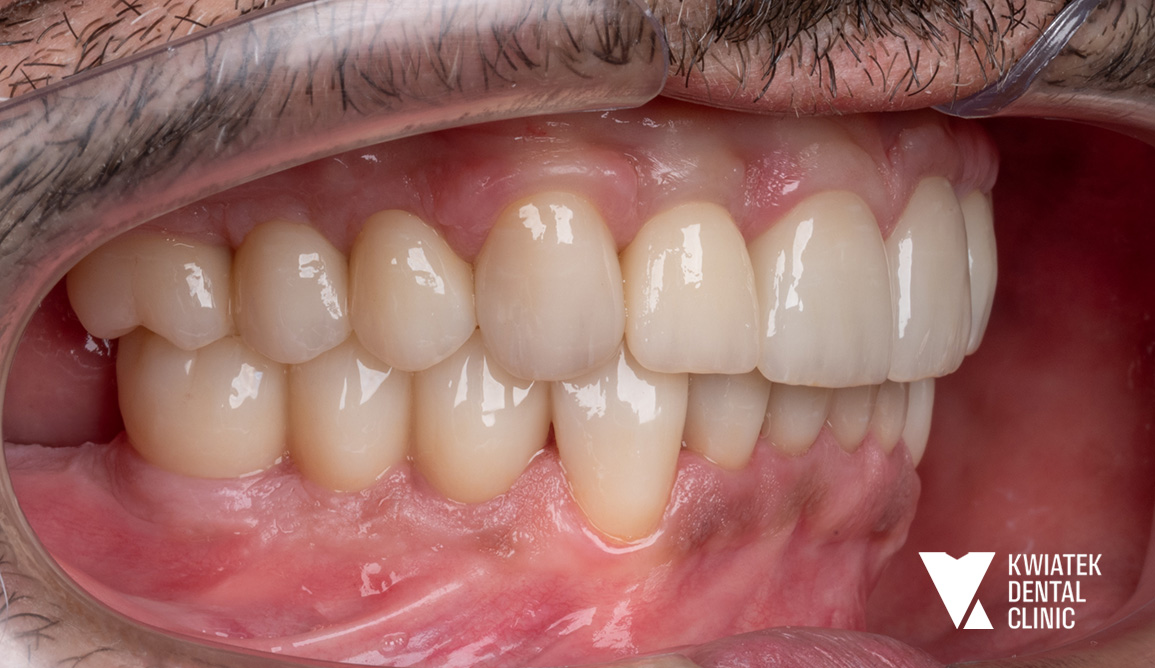

PO

W odcinku przednim przygotowano zęby pod licówki ceramiczne, które pozwoliły uzyskać idealne proporcje i naturalny wygląd. Na etapie gojenia Pacjent korzystał z koron tymczasowych, które umożliwiały funkcjonowanie i stopniowe przyzwyczajenie się do nowego zgryzu.

Po integracji implantów wykonano korony ceramiczne na implantach oraz korony pełnoceramiczne na zębach własnych, dzięki czemu cały uśmiech zyskał harmonijny, estetyczny wygląd.

Kompleksowe podejście pozwoliło przywrócić Pacjentowi pełen komfort i estetyczny uśmiech oparty na solidnych, nowoczesnych rozwiązaniach stomatologicznych.